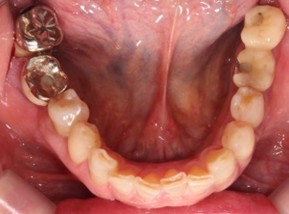

70代 女性

治療前

治療後

治療後- リスク・副作用

- 術後疼痛、歯肉腫脹

- 治療の費用

- 合計¥587,000(税込)

【内訳】

インプラント(1本)¥440,000

その他費用¥147,000

(薬・注射・レントゲン・CT・データ分析・サージカルステント・血液検査) - 年齢/性別

- 70代/女性

- 患者の具体的な症状

- 下顎の奥歯が義歯で噛みづらいため、インプラント治療を希望

- 検査方法

- コーンビームCT、レントゲン撮影

- 診断結果

- 左下6欠損

- 治療詳細

- 左下6インプラント埋入1本、骨造成なし、局所麻酔

- 通院回数

- 8回

- 治療期間

- 6か月